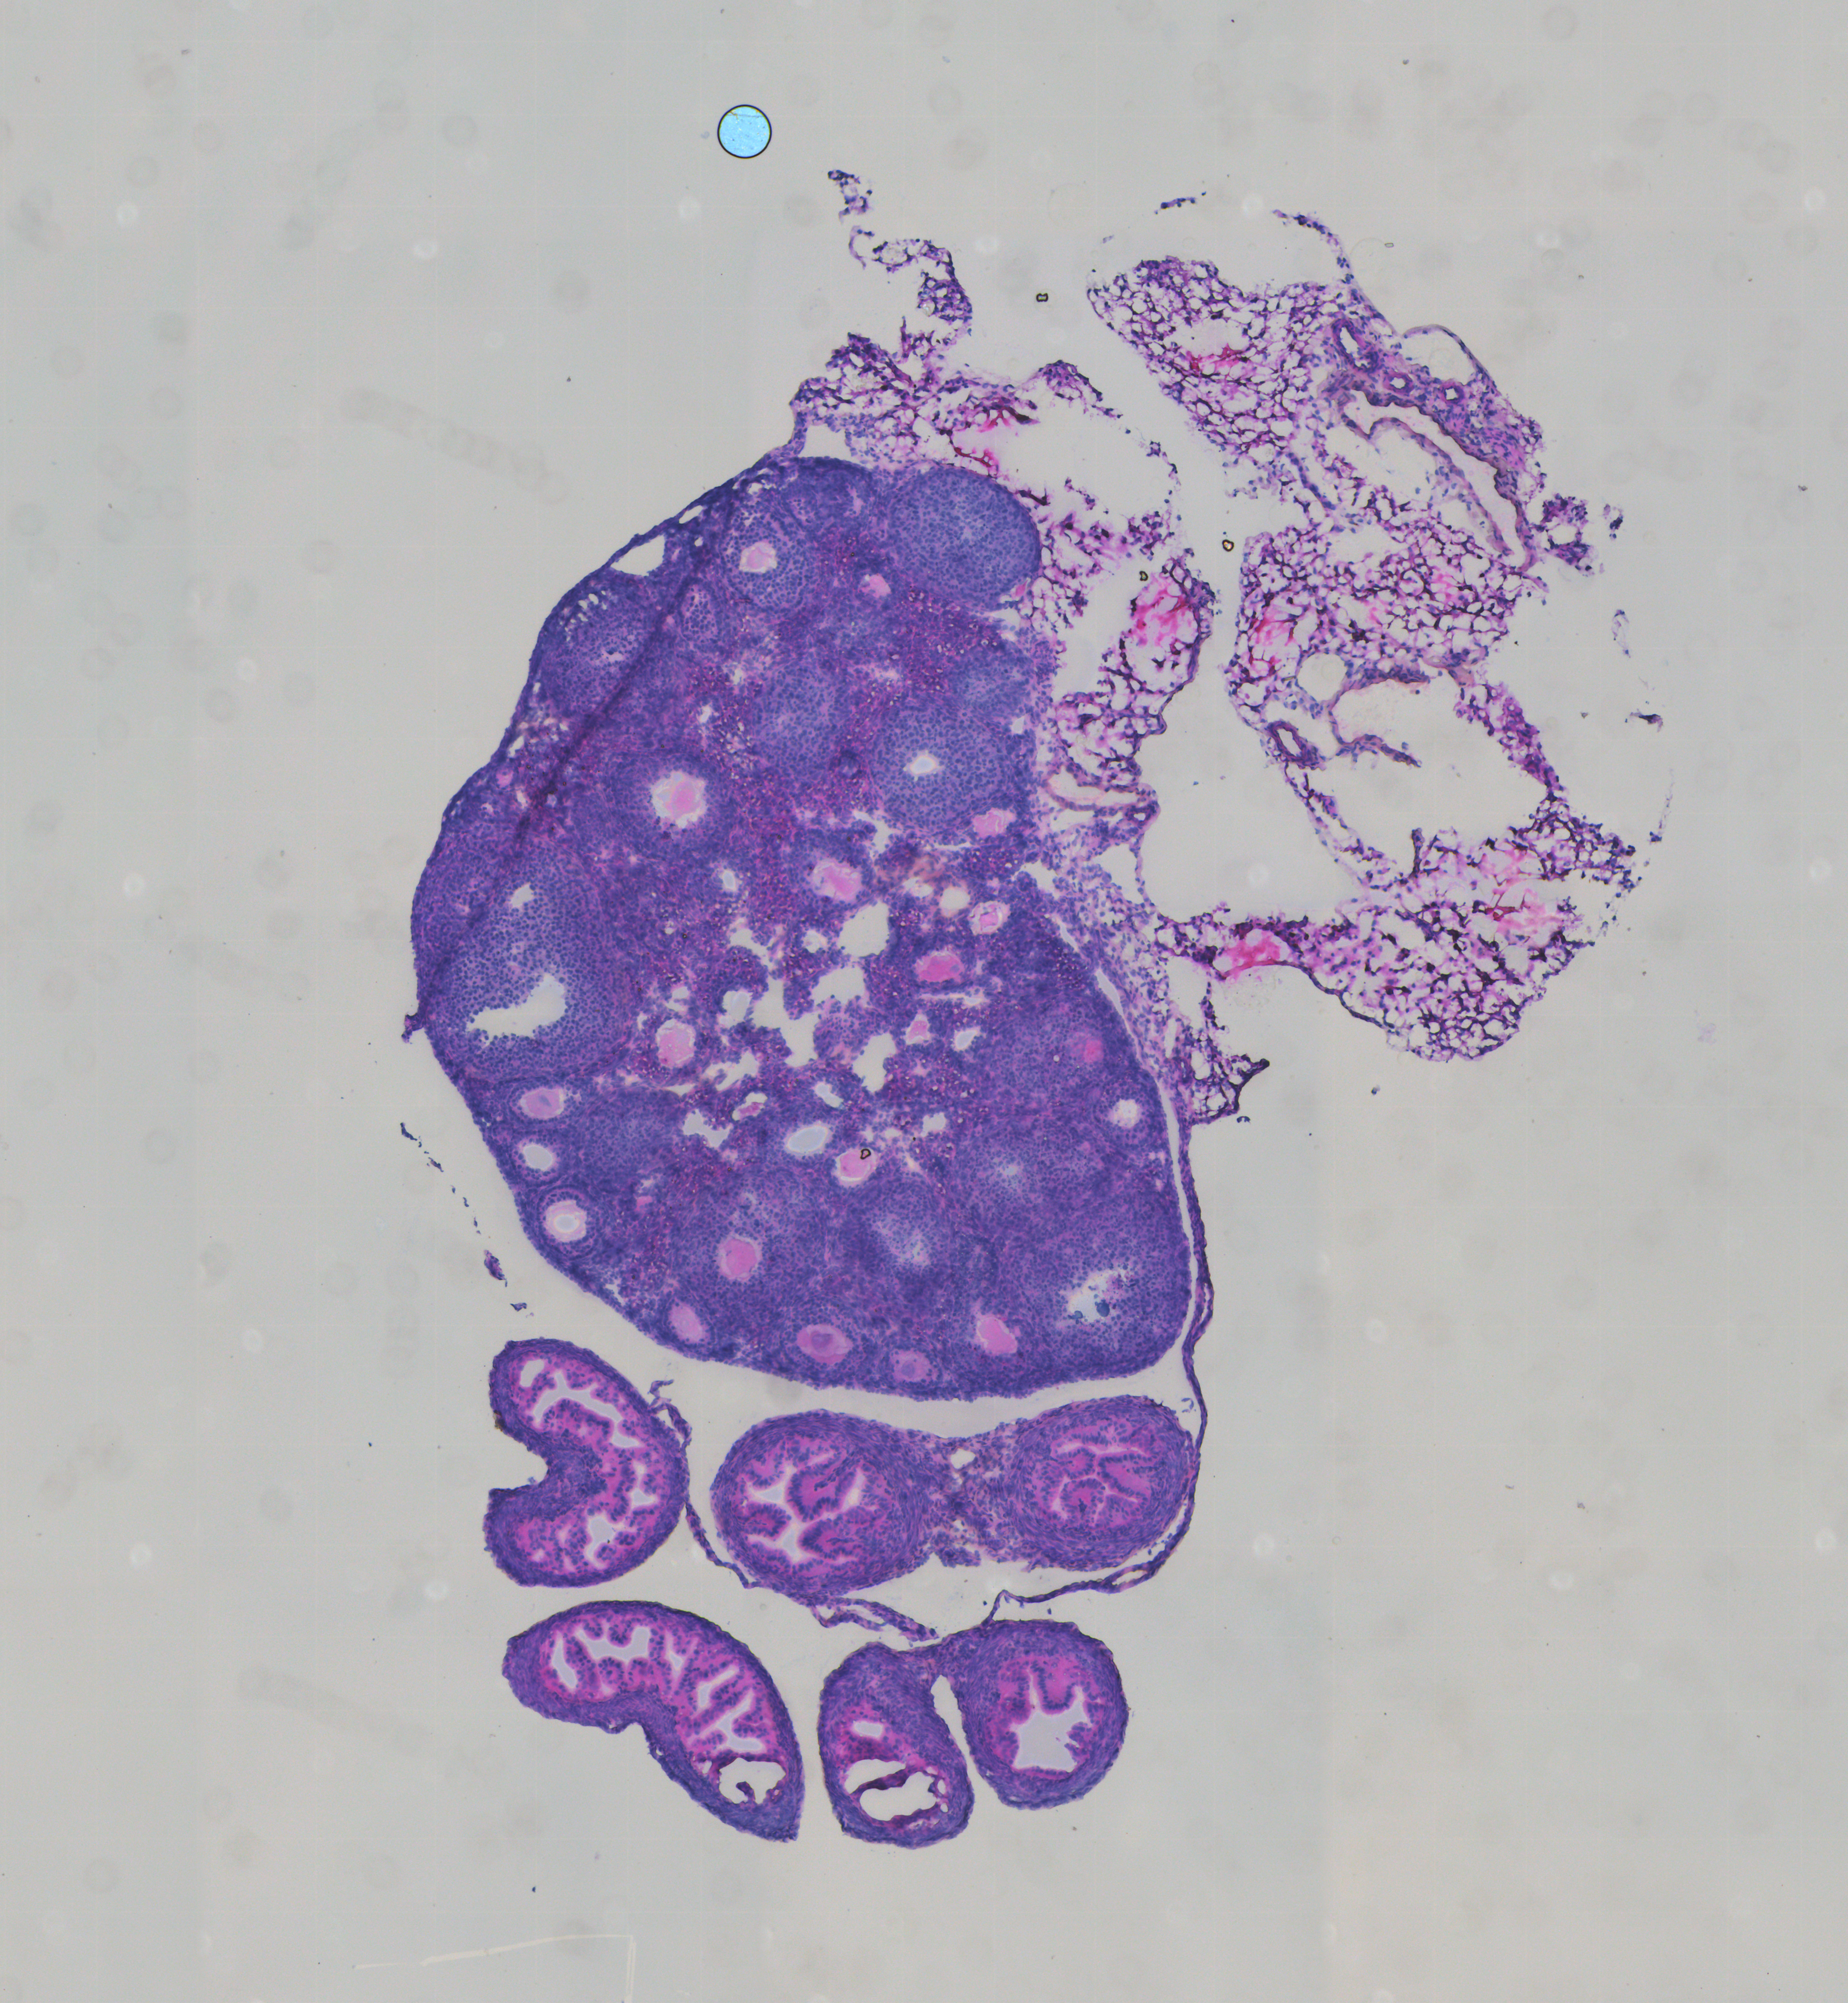

### Hematoxylin & eosin staining (H\&E) image

Hematoxylin and Eosin stain (H\&E stain) is a widely used tissue stain that provides histologic information for medical diagnosis and is considered the gold standard. Hematoxylin mainly stains cell nuclei in purplish blue, and eosin colors cytoplasm and extracellular matrix in different shades of pink. By integrating spatially resolved sequencing-based feature data generated from Stereo-seq with the H\&E staining image, the morphology of cells can be linked with spatially localized feature expression. The combined use of histology images and feature expression co-representation increases the amount of information that a tissue slice can provide.

<figure><img src="https://content.gitbook.com/content/EJfu1dx8qHVkvX5muz7N/blobs/Vbphs6RhuGlY6O9yEcbl/H&#x26;E.png" alt="" width="375"><figcaption><p>H&#x26;E</p></figcaption></figure>